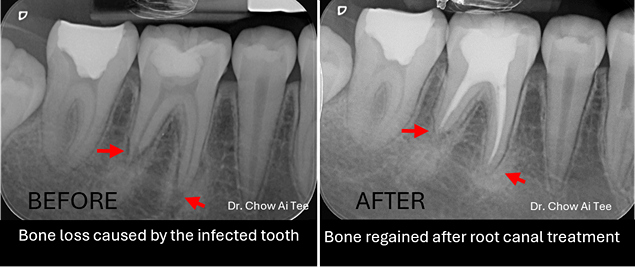

Fortunately, pulling out a tooth is no longer the go-to solution. In most cases, root canal treatment (endodontic therapy) offers a way to preserve the natural tooth. During this procedure, the dentist removes damaged and infected pulp tissue from the tooth, ensuring proper oral function. The first step involves assessing the tooth, identifying the problem, and planning the treatment. Dental X-rays and other diagnostic tools help determine the extent of damage.

A thorough review at one year is essential to ensure that the treatment has been successful, checks for any signs of infection or complications, and confirms that the tooth is healing properly.